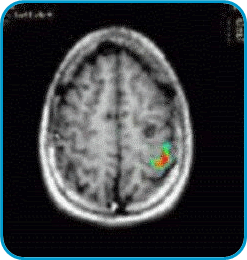

In the left image there is a little cyst in the left hemisphere (seen at the right side of the brain as a round black shape). This lesion produced seizures. The surgeon needs to know the location of the cortex in charge of the movement of the hand. This fMRI shows in colors the area used for the movement of the right fingers in a tapping task. This enables the neurosurgeon to extract the lesion without removing the area needed to move the hand.